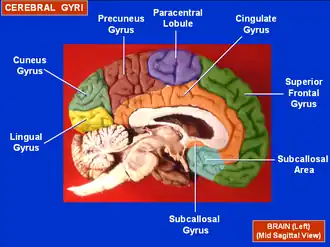

The cuneus (from Latin 'wedge'; pl.: cunei) is a smaller lobe in the occipital lobe of the brain. The cuneus is bounded anteriorly by the parieto-occipital sulcus and inferiorly by the calcarine sulcus.